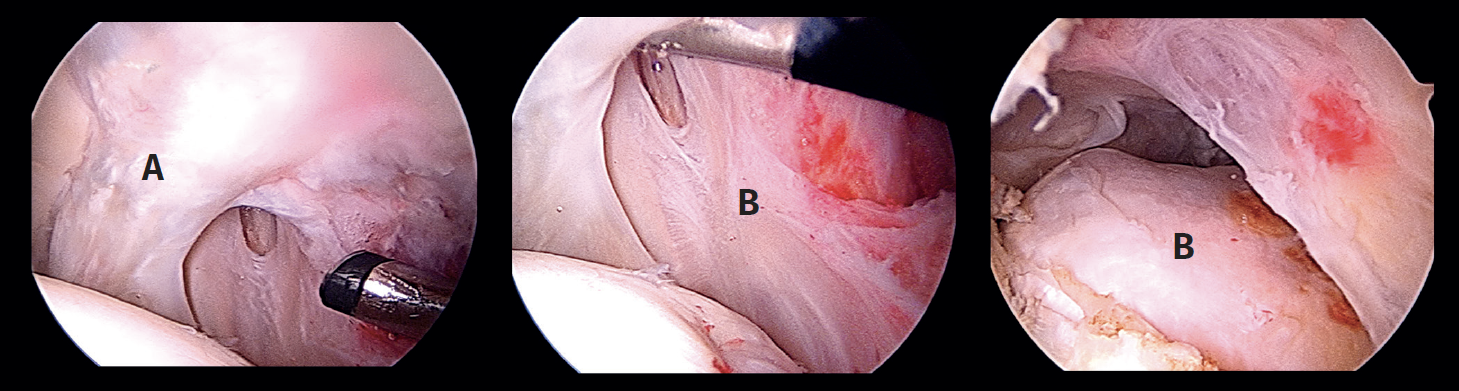

Arthroscopy, labral check, preparation or the acetabulum and of the capsule zone

Once the anterolateral and modified anterior portals have been established, an interportal capsulotomy is performed to allow handling of the instruments within the joint. The vision portal during most of the surgery is the anterolateral portal. During the procedure a degenerated labrum is observed, with re-ruptures, adherences and an impaired chondrolabral junction. In addition, an important anterior capsule defect is observed. This combination clearly determines the loss of joint sealing (Figure 3). In a first step we remove the deficient labrum in the anterosuperior zone and the acetabular margin is gently refreshed with a 4.0 mm round bur (Stryker®) to expose the proximal anatomical insertion of the iliofemoral ligament: from the upper part of the iliopsoas recess (approximately in the 2:30 o'clock position) to the anteroinferior portion of the anteroinferior iliac spine (AIIS) (approximately in the 12 o'clock position). The remaining capsule tissue in the zona orbicularis(ZO) is refreshed with a synoviotome in preparation for the distal anastomosis. Then, the hip is examined through flexion and rotation to evaluate the capsule defect in these positions. Through the DALA we place two 2.1 mm PressFT® (Conmed) suture anchorings loaded with Hi-Fi number 2 suture in the acetabular margin proximal to the labrum, in the insertion zone of the iliofemoral ligament, at the 12 and 2:30 o'clock positions, and the sutures are exteriorized through the proximal middle anterior portal (PMA) (Figure 4). These sutures will be used for the acetabular or proximal insertion of the capsule dermal graft.